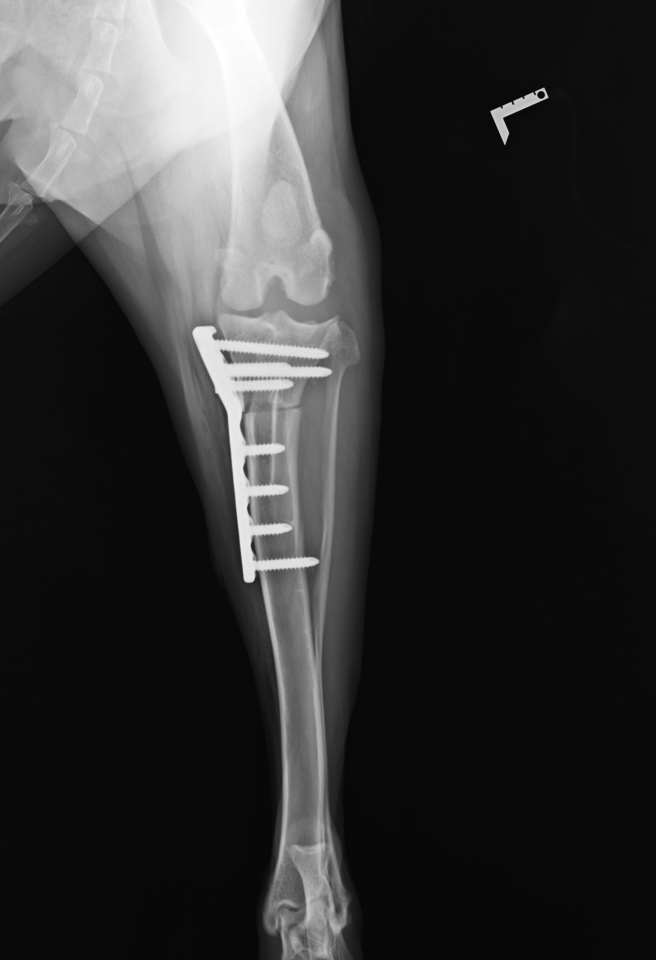

翌日の検査結果で十字靱帯完全断裂と診断され、6月29日に靭帯損傷の(関節鏡+TPLO手術)になりました。

私、護得久 美奈が飼っているシェパード雄、4歳が6/29に左膝前十字靭帯損傷のため(関節鏡+TPLO術)をうけました。(県外で)

左後脚十字靱帯断裂(関節鏡+TPLO術) 743.622円 完了

左膝後脚前十字靱帯断裂(関節鏡+TPLO術)743.622円 完了